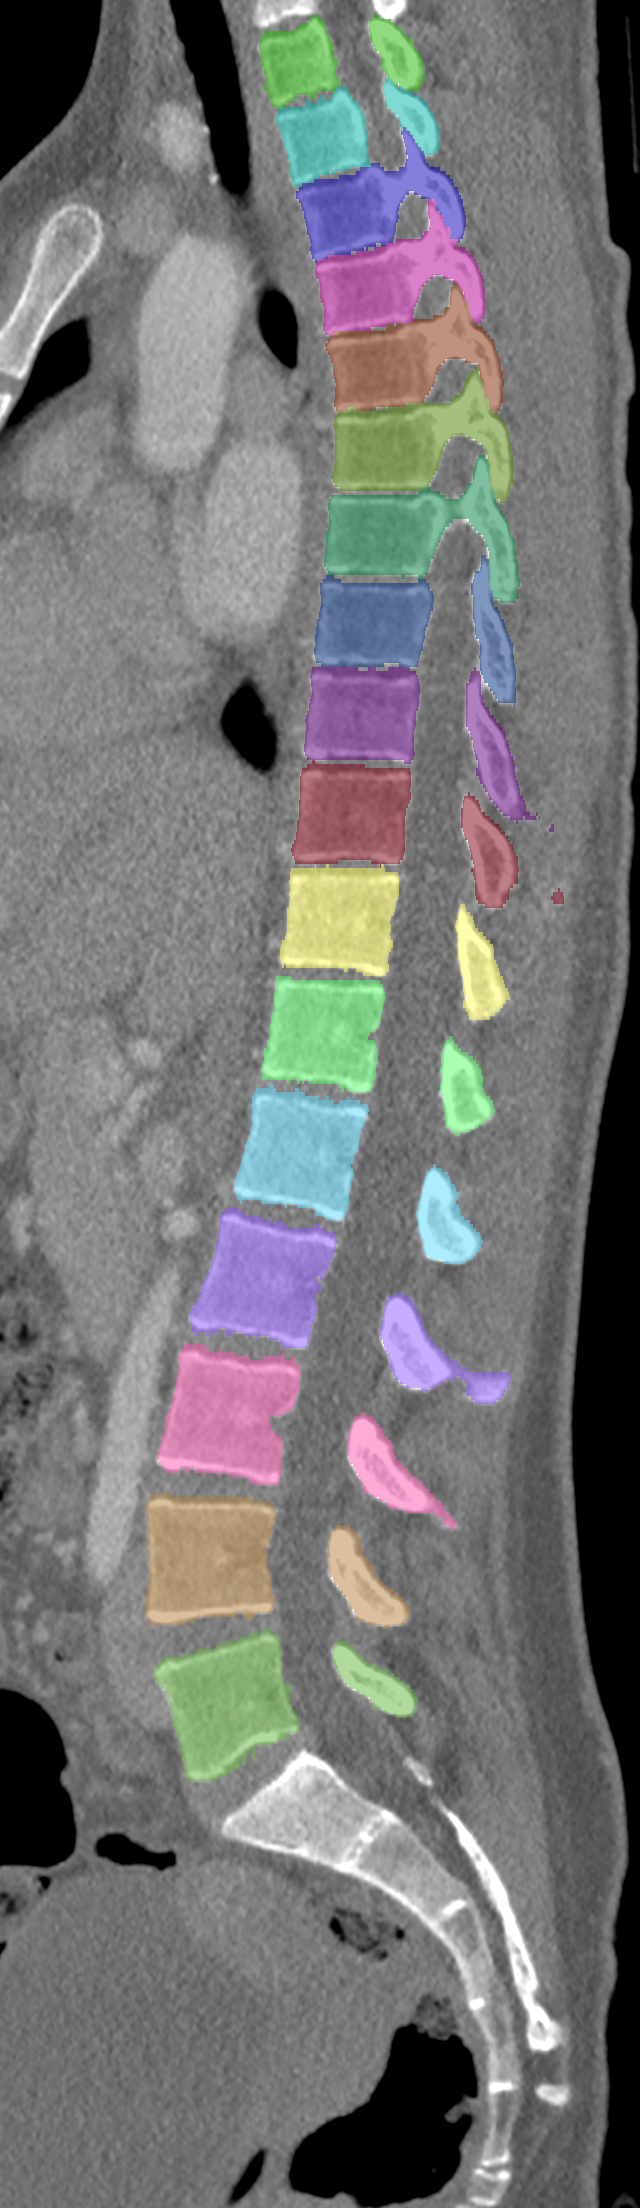

Normalized CT images and reference segmentations of thoracic and lumbar vertebrae from the CSI 2014 workshop

Description

This is the dataset of the vertebra segmentation challenge of the CSI 2014 workshop that was held in conjunction with MICCAI 2014.

- Vertebrae have been anatomically labeled (8 = T1, 9 = T2, ..., 24 = L5)

- Because not always all visible vertebrae were segmented in the original data, only segmentations of the thoracic and lumbar vertebrae have been retained